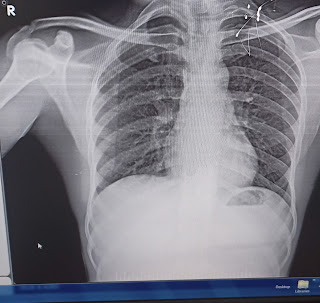

Chest Xray:

07/01/2023

09/01/2023